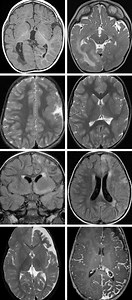

File:New-Onset-Refractory-Status-Epilepticus-with-Claustrum-Dama

…

May 21, 2017

wikimedia.org